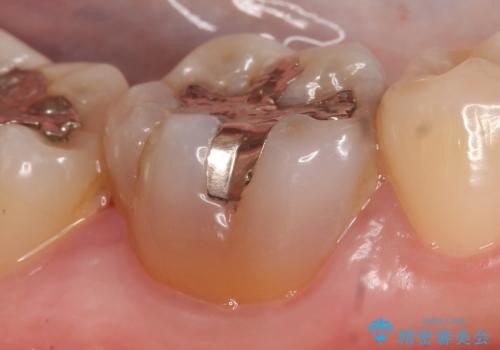

- 右下6番目の歯の舌側に虫歯があるので治療して欲しいといらっしゃった方の症例です。

古い銀歯及び虫歯を除去後、セラミックインレーにて修復を行いました。